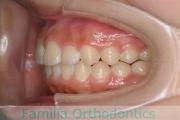

No.23V-100

- 上顎前突

- 叢生

- 14歳

- 女性

- 上:

- 44

- 下:

- 55

- 主な使用装置:

- FEA

歯並びを治したいということで来院されました。下あごがやや右側に偏位して後退している、上顎前突(出っ歯)でした。上下左右から小臼歯を抜歯して、歯科矯正用アンカースクリューを併用したマルチブラケット法にて治療を行いました。約2年、24回の来院をしていただきました。

下顎の後退はいびきなどの上部気道の障害が出やすいと考えられます。